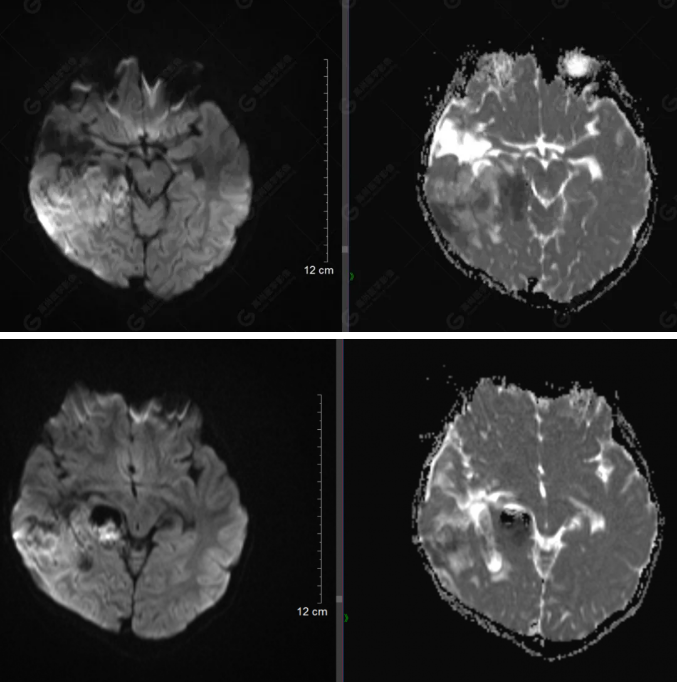

右側(cè)顳葉腫瘤切除術(shù)后(具體不詳):右側(cè)顳部骨質(zhì)不連續(xù)呈術(shù)后改變,右側(cè)顳葉術(shù)區(qū)見片狀長T1長T2信號影,F(xiàn)LAIR呈低信號;術(shù)區(qū)后方右側(cè)顳枕葉見一巨大占位性病變影,邊界欠清,大小約6.2×5.8×4.3cm(前后×左右×上下),信號不均勻,T1WI呈等稍低信號間雜少許高信號,T2WI呈高稍低混雜信號,DWI示部分病灶彌散受限,相應(yīng)ADC圖減低,磁敏感序列見部分呈極低信號,增強掃描可見明顯不均勻強化,鄰近硬腦膜及小腦幕增厚并明顯強化;另延髓右前方及右側(cè)橋小腦角區(qū)見一不規(guī)則形異常信號影,大小約3.2×1.3×3.7cm(左右×前后×上下),呈長T1稍長T2信號,F(xiàn)LAIR呈等信號,DWI未見受限,增強后明顯均勻強化,鄰近腦膜明顯強化。鄰近腦實質(zhì)及右側(cè)顳角明顯受壓;左側(cè)大腦半球未見局灶性信號異常,中線結(jié)構(gòu)稍左移。

右側(cè)顳葉腫瘤切除術(shù)后:現(xiàn)術(shù)區(qū)后方右側(cè)顳枕葉及延髓右前方占位,右側(cè)顳枕部硬腦膜及小腦幕明顯強化,結(jié)合既往影像資料,考慮為胚胎源性惡性腫瘤,如非典型畸胎樣/橫紋肌樣瘤(AT/RT)或原始神經(jīng)外胚層腫瘤(PNET)。